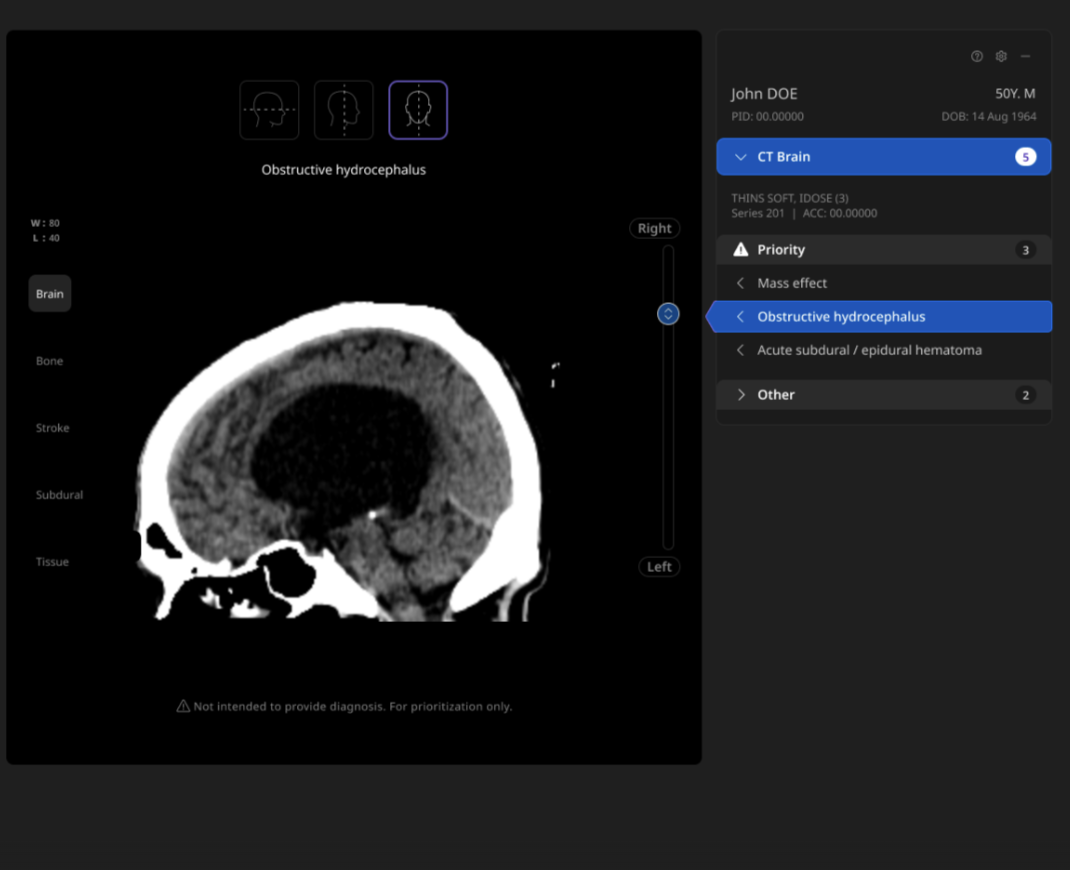

Harrison.ai Comprehensive Care is a breakthrough imaging AI solution for chest X-rays and non-contrast head CT that identifies 12 findings in under 90 seconds, reducing stress from chaotic worklists by surfacing emergent and incidental findings for review – all within the workflow you’re used to.